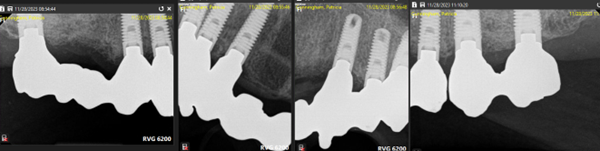

When all of a patient’s teeth are failing but dentures aren’t an option, we perform “staged therapy.” First, every tooth is prepared and fitted with a full-arch temporary splint (Fig. 1). Next, select teeth are extracted and replaced with implants, while the remaining teeth continue to hold the temporary (Fig. 2 & 3). In Stage II, abutments are seated on existing implants, the remaining teeth are extracted, and implants placed (Fig. 4). Finally, a permanent fixed splint is secured on all implants (Figs. 5 & 6).

Fig. 5: Stage III All Implants Restored with a Permanently Fixed Final Splint

Fig. 6: Final Splint in Place Over Full Arch Implants

Stage III: The remaining implants are restored with additional implant abutments and the final crowns (Figs. 5 & 6).